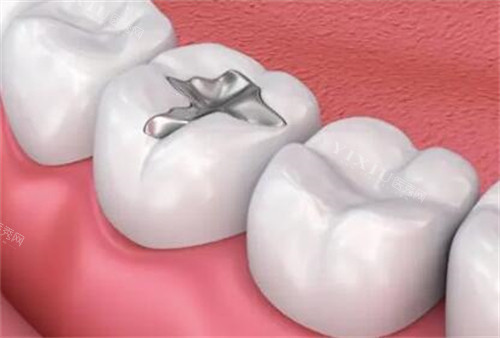

嵌体修复适合较大的龋洞,当牙齿损坏程度较大,无法单纯补牙时考虑。

这是一种定制化的修复方式,尤其瓷嵌体生物相容性好,更加耐用美观。价格通常在1580-3500元/颗。